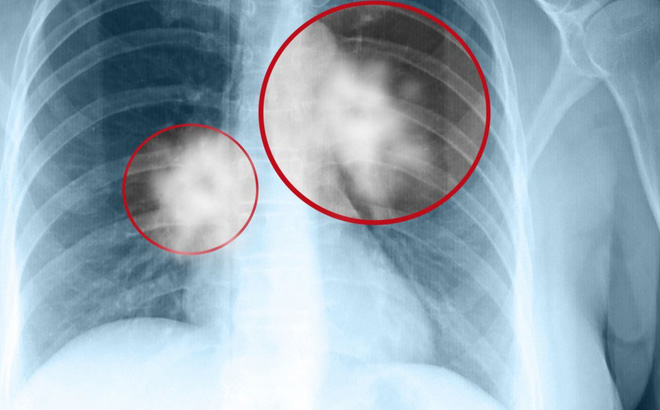

Theo các bác sĩ chuyên khoa ung thư trên kênh Sức khỏe/Sohu (TQ), có những bệnh nhân đã được thông báo rằng họ không có gì bất thường về kết quả X quang phổi khi khám sức khỏe định kỳ vào năm ngoái. Nhưng năm nay, khi họ kiểm tra CT phổi và thực sự choáng váng khi bị chẩn đoán ung thư phổi. Chuyện gì đang xảy ra?

Ví dụ, Chụp X-quang phổi và CT phổi có thể có độ nhạy tương đối khi muốn phát hiện các yếu tố liên quan đến bệnh lao. Bệnh viêm phổi thông qua chụp X quang phổi vẫn có thể nhận thấy kết quả tương đối rõ ràng, nhưng lại đặc biệt khó phát hiện ra dấu hiệu ung thư phổi sớm.

Độ rõ và độ tương phản của kết quả chụp X quang phổi làm giảm khả năng nhìn thấy bệnh đi rất nhiều, vì vậy các bác sĩ chuyên nghiệp sẽ khuyên dùng cách chụp CT phổi nếu bạn là người có nguy cơ mắc ung thư phổi nhiều hơn những người khác.

Hút thuốc lá chính là nguyên nhân chính dẫn đến ung thư phổi. Đối với những người hút thuốc trong thời gian dài, tốt nhất nên kiểm tra CT phổi hàng năm. Nói chung, nếu chỉ khám phổi thông thường hoặc chụp kiểm tra X-quang ngực sẽ rất khó phát hiện ra các dấu hiệu ung thư phổi sớm.